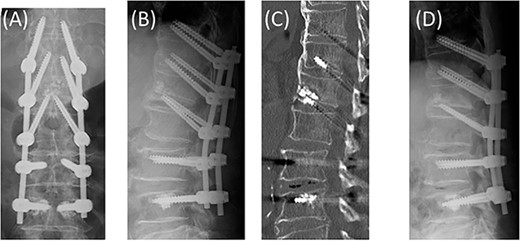

Posterior spinal fusion was performed under general anesthesia. Vertebroplasty with hydroxyapatite grafting was performed on the L1 vertebra via the DEPS trajectory from the L2 vertebra. Subsequently, using the DEPS technique, screws were placed at T12, L1, and L2, and conventional pedicle screws were placed at L3. Cement-augmented fenestrated pedicle screws were installed at L4 to enhance the pull-out strength (Fig. 2A–C)).

Vertebroplasty with hydroxyapatite grafting on the L1 vertebra via the DEPS trajectory from the L2 vertebra. The DEPS technique to T12, L1, and L2. Conventional pedicle screws to L3 and cement-augmented fenestrated pedicle screws to L4 (A, B, C). No screw loosening or kyphosis progression at 6 months postoperatively (D).

Postoperatively, the back pain improved, and external fixation using a frame-type thoracolumbar corset was also performed for 6 months. No screw loosening or kyphosis progression was noted at 6 months postoperatively (Fig. 2D).